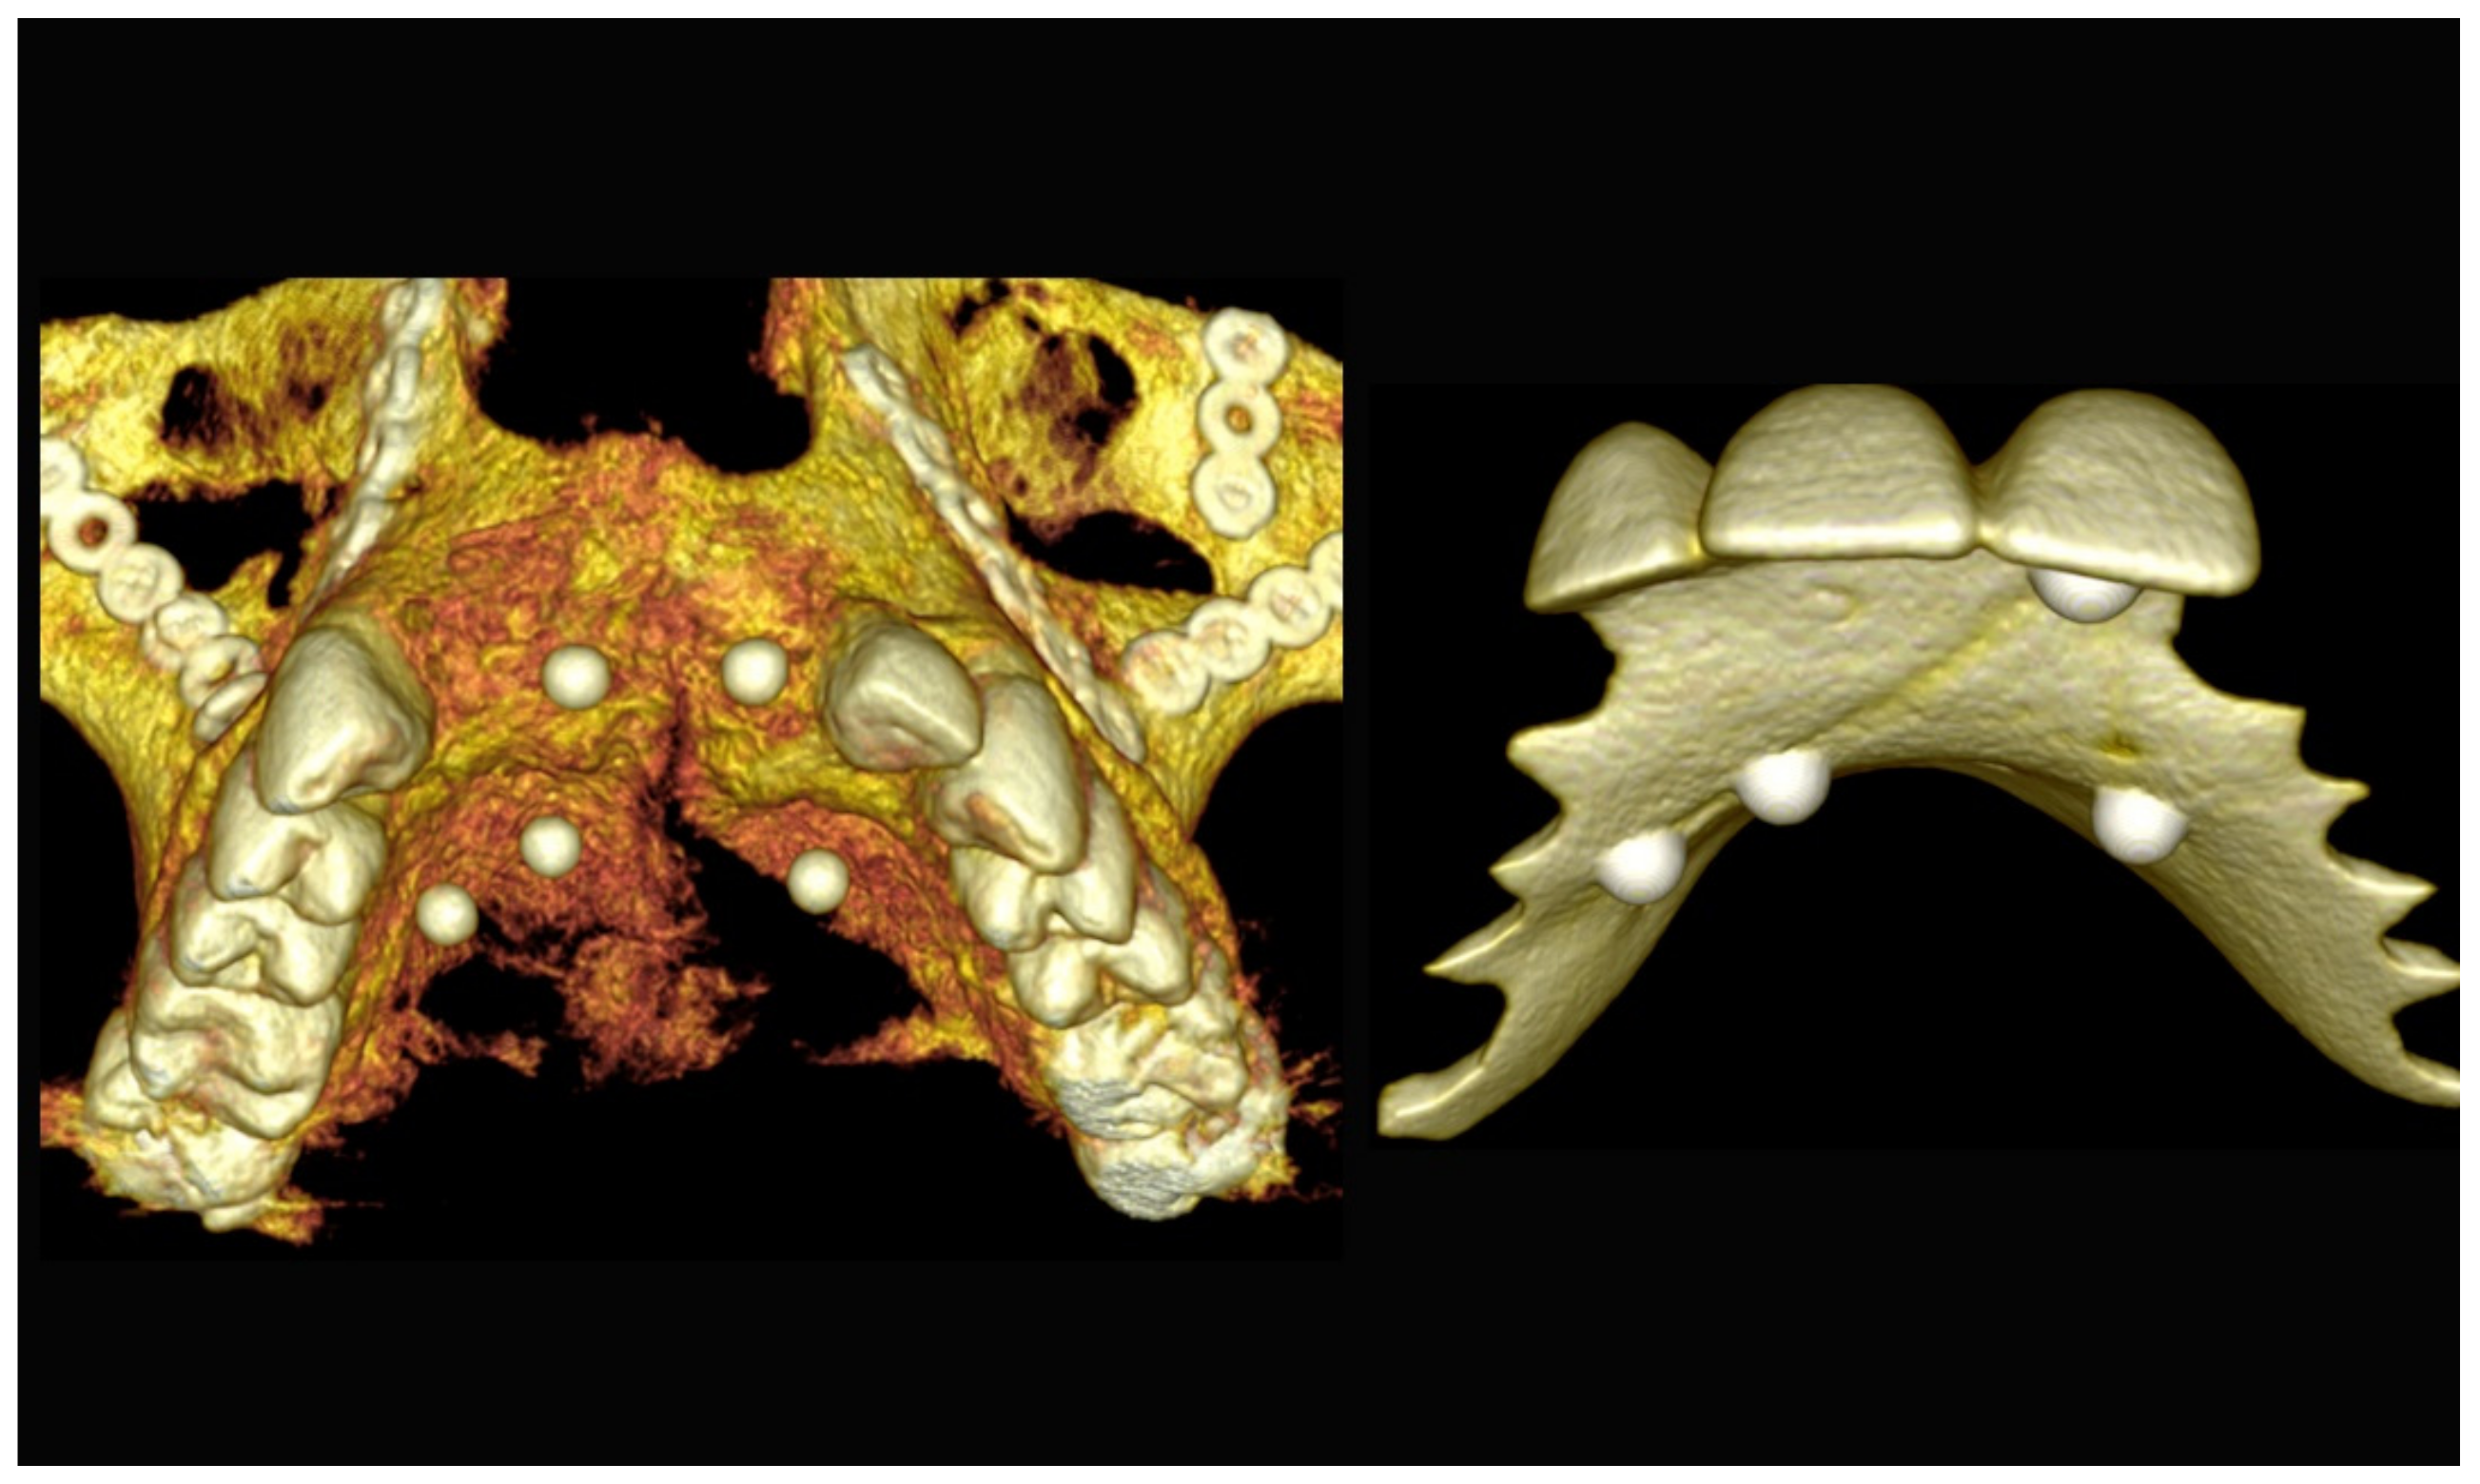

Figure 4.

Planning of the number, the diameter, and the axis of the implant with respect to the design of the final prosthesis.